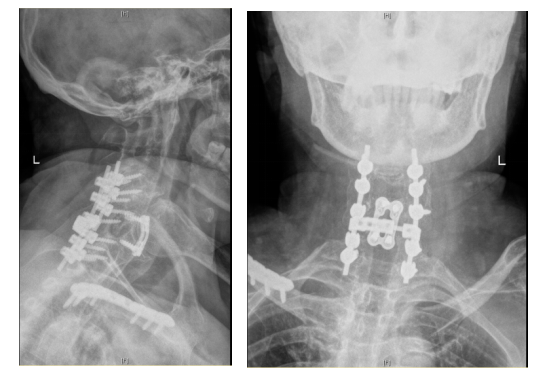

术后复查CT影像结果

手术室、麻醉科等相关科室高效联动,医护密切配合,小心翼翼地协助患者调整颈部角度,多位资深麻醉医生紧密配合成功插管,在保障患者安全、避免脊髓二次损伤的前提下,尽可能扩大手术视野。手术中,曾浩带领手术团队凭借精湛的医术和丰富的临床经验,在狭窄的操作空间内精准操作、成功完成手术,并最大限度地保护了受损的脊髓神经,为患者的康复争取了希望。

面对挑战,团队决定实施颈椎前路联合后路这一高难度手术,以解除脊髓压迫,充分固定颈椎三柱损伤,最大限度促进脊髓功能恢复。